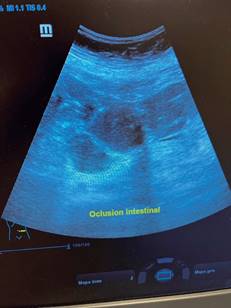

El cirujano general aborda particularmente problemas clínicos que incluyen el aparato digestivo, el cuello, la pared abdominal y los trastornos del sistema circulatorio y el tórax. Un artículo publicado en 2008, por Lindelius,15 demostró que la implementación del ultrasonido por parte del cirujano general en casos de dolor abdominal agudo incrementó en 7.9% la precisión diagnóstica. En la consulta cotidiana de la especialidad, incorporar el rastreo sonográfico al área explorada agrega minutos al examen clínico que aportan datos de notable valor por la objetividad y precisión. El abdomen suele ser el sitio que los cirujanos generales exploramos con más frecuencia. Es posible en una consulta cotidiana hacer todo el protocolo de ultrasonido de abdomen superior en minutos, que incluye ambos cuadrantes superiores y los flancos, pudiendo observar el hígado, la vesícula y los conductos biliares, ambos riñones, el bazo, parte del páncreas y, con ayuda del Doppler color, los principales vasos de la región como la vena cava inferior, la aorta abdominal, la vena porta, los vasos esplénicos y la arteria hepática. Puede haber limitantes como el contenido gástrico, el nivel de llenado de la vesícula biliar o la constitución del paciente y su capacidad de cooperar con el estudio. Pero con la práctica cotidiana, se adquieren las destrezas y el refinamiento suficientes para lograr, con la experiencia acumulada, producir imágenes de relevancia diagnostica inmediata. En la fase de entrenamiento, contrastar nuestros hallazgos con información disponible en la red, con los colegas imagenólogos, o cirujanos ya experimentados en ecografía, permitirá la retroalimentación y la tutoría esenciales de toda curva de aprendizaje. Tradicionalmente se consideraba que aquellos órganos que contienen una mezcla de líquido y gas (intestino, estómago) no son valorables por ultrasonido, el gas produce un efecto rarefacción, ya que no comprime las ondas como un tejido solido o un medio líquido, la señales entonces se dispersan impidiendo que regresen como ecos y permitan al procesador formar una imagen congruente con el órgano explorado. Sin embargo, cuando esta condición cambia como consecuencia de un estado patológico, es posible identificar el contenido intestinal o el gástrico y darnos una idea más aproximada de lo que realmente está ocurriendo en ese abdomen. Podemos, por ejemplo, saber si un estómago está lleno de líquido, o si el intestino contiene residuo sólido, líquido o gaseoso. Los equipos actuales pueden incluso ver en detalle la pared intestinal cuando ésta esté dilatada. Se puede distinguir cuando el colon está ocupado de líquido a nivel del flanco izquierdo como podría ser en una colitis amebiana o en una oclusión intestinal,16 donde se observa dilatación del intestino delgado ≥ 25 mm, el peristaltismo anormal, la presencia de líquido libre intraperitoneal y el edema de la pared intestinal (Figura 2). En casos de dolor abdominal agudo, el ultrasonido puede, en forma inmediata, permitir diagnósticos diferenciales como el hallazgo de una dilatación pielocalicial por nefrolitiasis (Figura 3), o un aneurisma de la aorta abdominal (Figura 4). Un estudio prospectivo realizado en Irvine, California,17 encontró que la a capacidad diagnóstica del médico de primer contacto practicando el ultrasonido para detectar una colelitiasis tiene una especificidad de 87% y una sensibilidad de 82%, mientras que la prueba de ultrasonografía realizada por radiología tuvo sensibilidad de 83% y una especificidad de 86%. Es decir, que, ahorrando tiempo al paciente, el diagnóstico de colelitiasis es factible agregando unos minutos al examen físico inicial. En casos de apendicitis, el método diagnostico considerado como el estándar de oro es la tomografía axial computarizada (TAC). Sin embargo, tiene inconvenientes como su disponibilidad, su costo, el riesgo de radiación en niños y pacientes embarazadas. En tales situaciones, sobre todo en niños, sexo femenino o pacientes delgados, el ultrasonido es una poderosa herramienta que complementa el examen clínico inicial. Las ventajas del ultrasonido frente a la tomografía serian su ubicuidad (ya está en la sala de emergencias), el bajo costo, la ausencia de radiación y el diagnóstico diferencial con causas ginecológicas o genitourinarias de dolor. En apendicitis, la sensibilidad y especificidad de la TAC es de 99.4% y 80.0%, respectivamente. Para el ultrasonido, la sensibilidad diagnóstica es de 83% y la especificidad de 90%. La tasa de apendicectomía negativa es ligeramente mayor en el grupo de TAC que en el del ultrasonido, es decir, 7.1% (3/42) (TAC) en comparación con 4.67% (5/107) (ultrasonido). Hay que recalcar que el ultrasonido es operador dependiente. La experiencia y la calidad del equipo juegan un papel importante.18 La apendicitis tiene varios hallazgos característicos, como la pared edematosa y el aumento de grosor general. Se toman para criterios de positividad una estructura tubular aperistáltica no compresible que mide más de 6 mm de diámetro en el cuadrante inferior derecho (Figura 5).19-21

Figura 2: Dilatación de asas del intestino delgado con contenido anecoico (líquido), correspondiente a una oclusión intestinal.